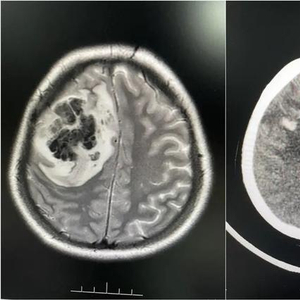

随后婷婷在当地医院查出右侧额叶占位性病变合并出血,医生怀疑是脑肿瘤卒中。陈女士说:“婷婷当时已经昏迷不醒,都剃了头发准备手术。”为寻求进一步诊疗,2月底,家人陪同婷婷来到广东三九脑科医院。

医院接诊医生仔细分析后,发现婷婷颅内病变不是脑肿瘤。结合病史和相关影像资料,该院神经内一科副主任匡祖颖初步怀疑是颅内静脉窦血栓,进一步完善全脑血管造影,证实是颅内静脉窦血栓形成合并出血